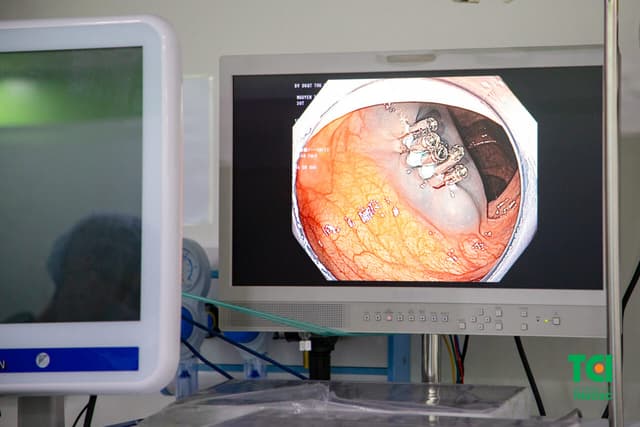

Các phương pháp chẩn đoán trào ngược dạ dày thực quản

Bệnh trào ngược dạ dày thực quản (GERD) là một tình trạng khi acid dạ dày và dịch vị trào ngược lên thực quản, gây ra nhiều triệu chứng khó chịu. Để chẩn đoán GERD, có nhiều phương pháp chẩn đoán được sử dụng. Vậy các phương pháp chẩn đoán trào ngược dạ dày thực […]